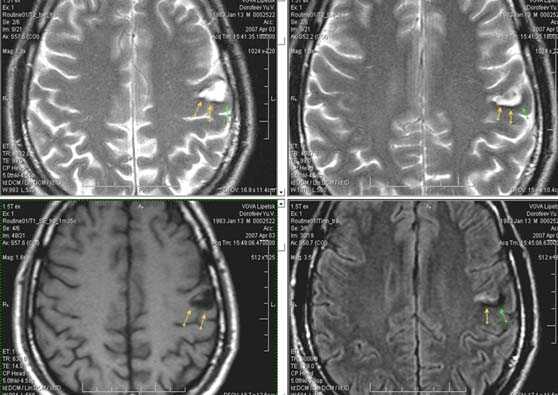

Первые часы ОНМК. Изменения в области правого островка демонстрирует только программа DW insult.

Зона подострого ишемического НМК, в бассейне правой средней мозговой артерии. В режиме Т1 визуализируется симтом «вуалирования»- изоинтенсивность МР-сигнала.

Подострая стадия ишемического НМК. При внутривенном контрастировании определяется накопления КВ в бороздах на уровне зоны ишемии (гиральный тип усиления).

Лакунарное ишемическое ОНМК на фоне хронической сосудистой недостаточности.

Некоторые инфаркты при дисциркуляторной энцефалопатии протекают бессимптомно. Это «немые» инфаркты, которые, как правило, локализуются в глубоких отделах мозга и диагностируются только при МРТ. Этот случай показывает возможности выявление очага ограниченного ишемического ОНМК базальных ядер слева на фоне хронической ишемии.

Выраженная сосудистая энцефалопатия с наличием множественных очагов хронической ишемии, лакунарных постишемических кист. Программа ДВИ четко показывает фокус острого ОНМК в базальных ядрах справа на фоне лейкодистрофии.